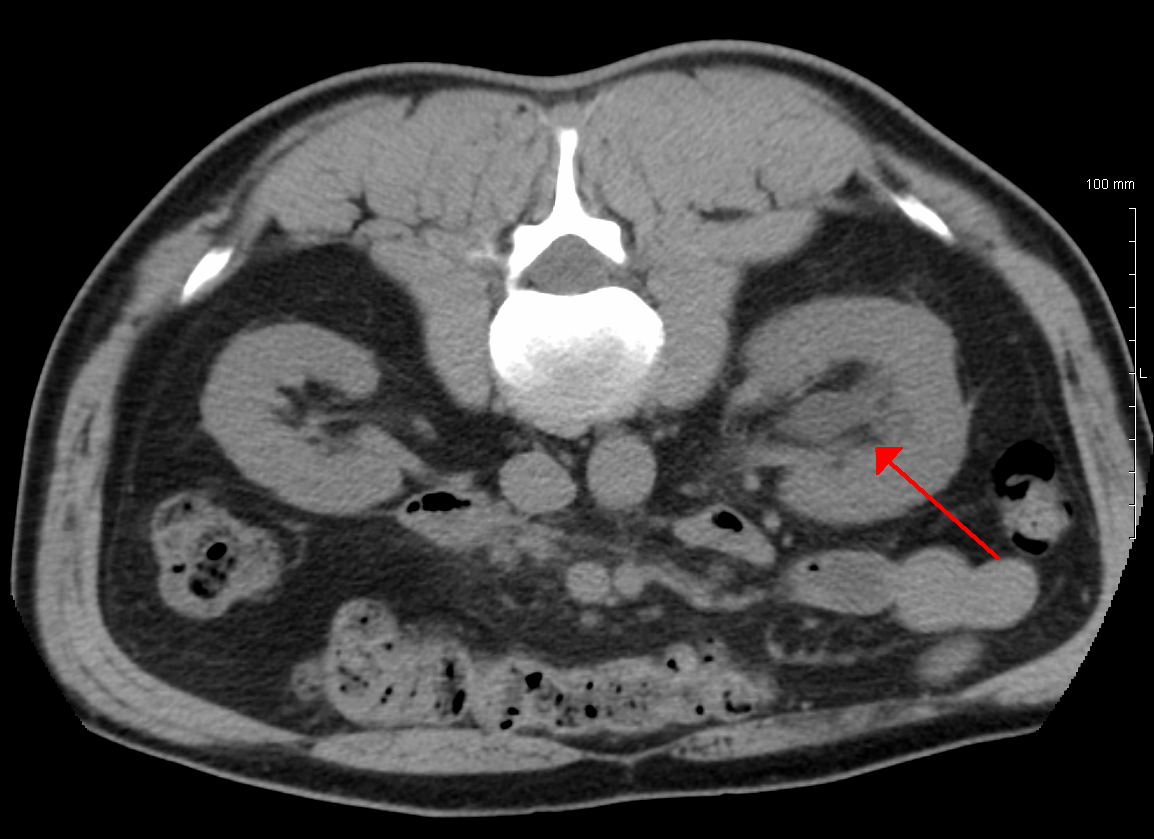

질병을 진단하려면 환자의 병력과 기타 신체 검사 정보를 알아야 한다. 이는 일부 영상 검사를 동반해야 한다. 일반적으로 초음파 검사를 사용하여 환자의 요로, 콩팥 등의 상태를 확인할 수 있다. 또한 CT 스캔과 MRI는 요로 및 폐쇄를 보다 명확하게 보여줄 수 있다.[8]

정맥 신우 조영술(IVU), 신장 초음파 검사, CT, MRI 등의 영상 검사도 중요하다. 초음파 검사는 요관과 신장을 시각화하고 수신증 및 수뇨관증 유무를 확인하는 데 유용하며, IVU는 막힘의 해부학적 위치 평가에 유용하다. 순행 또는 역행 신우 조영술은 IVU와 유사한 소견을 보이면서 치료 옵션도 제공한다. 실시간 초음파와 도플러 초음파 검사는 혈관 저항 검사와 함께 폐색이 요로 기능에 미치는 영향을 파악하는 데 도움이 된다.[12]

신 산통(소변에 혈흔이 섞인 옆구리 통증)의 초기 검사는 나선형 또는 헬리컬 CT 스캔이다. 이는 소변 흐름 폐색 여부와 다른 신장 기능도 보여준다. CT는 대부분의 결석을 확인할 수 있어 초기 검사로 흔히 선택되지만, 임신과 같이 방사선 노출을 피해야 하는 경우에는 사용하지 않는다.[13][14] 우연히 발견된 산전 수신증의 경우, 첫 검사는 산후 신장 초음파 검사다. 산전 수신증의 많은 사례가 자연적으로 해결되기 때문이다. 출생 후 며칠 이내에 시행하지만, 너무 이른 검사는 경미한 수신증을 놓칠 수 있어 4~6주 후 추적 초음파 검사를 권장하기도 한다.[15] 배뇨 방광 요도 조영술(VCUG)은 방광 요관 역류나 후부 요도 판막 같은 해부학적 이상을 배제하기 위해 시행된다. 수신증이 심각하고 요관 신우 접합부(UPJ) 또는 요관 방광 접합부(UVJ) 폐색이 의심되면, MAG-3 스캔과 같은 핵 영상 검사가 필요하다.[13]